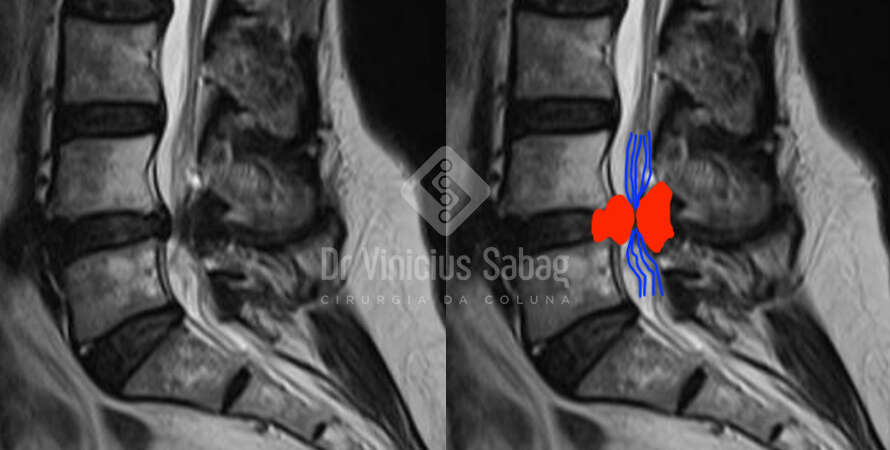

Ressonância magnética da coluna lombar evidenciando hérnia discal extrusa L5-S1 migrada inferior gerando compressão neurológica.

Comparativo entre as duas ressonâncias.